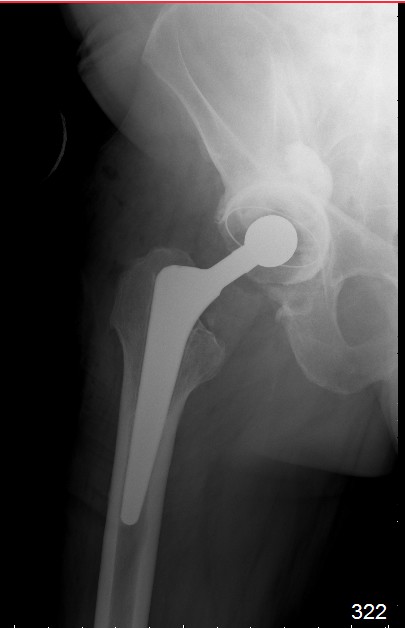

прилагаю рентген снимки сразу после операции в 2009г и февраль 2011г.